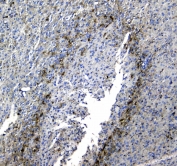

IHC testing of FFPE human glioma with SYT1 antibody at 1ug/ml. Required HIER: steam section in pH6 citrate buffer for 20 min and allow to cool prior to staining.